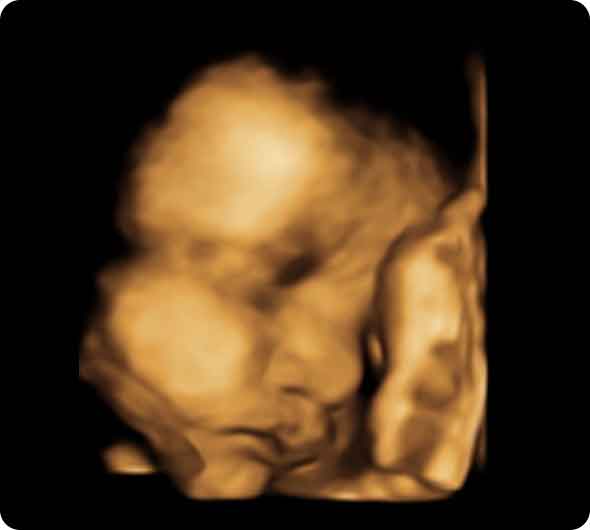

4Dエコー外来では、胎児の動きが立体的(3D)に観察でき、さらに経時的(4D)要素を加えることにより、胎児の動いている姿・表情を立体的な動きで見ることができます。

お腹の中の赤ちゃんの様子、成長過程をご覧いただけます。